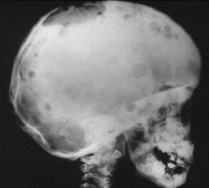

Thalassemia 地中海/海洋性貧血

- α-Thalassemia

- α 出問題, 只有 4β 或 2β2δ

- 嚴重,易死胎

- β-Thalassemia

- β0: 較常見,完全無 β

- β+: 較少見, β 少

- 症狀

- Sunrise skull bone (Hair-on-end)

- 造血細胞/ 骨增生

- 長骨骨隨增生

- 扁平骨變寬

- 血色素沉積: 心、胰、脾